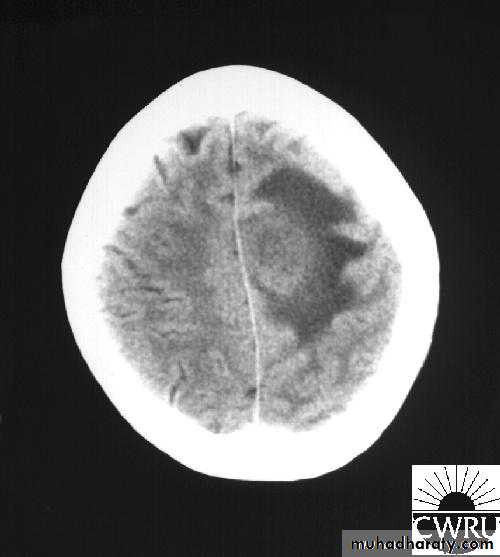

Bacterial Meningitis with cerebral oedema